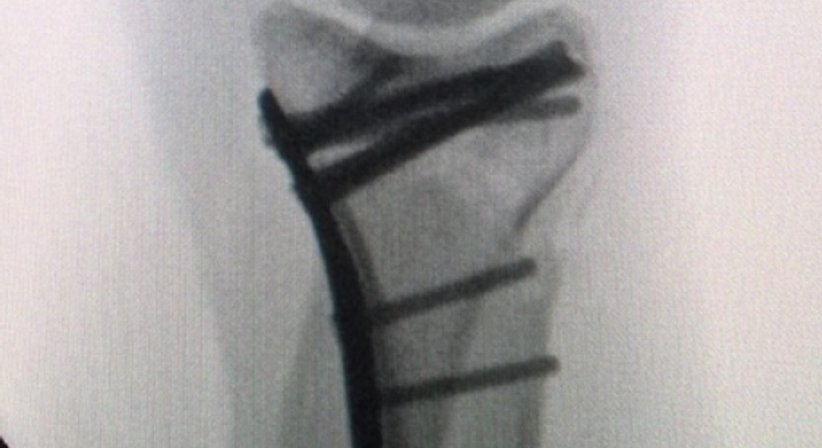

Versorgung von Knochenbrüchen

Osteosynthesen - OA Dr. Andreas Mondl - Unfallchirurg Wien 1220